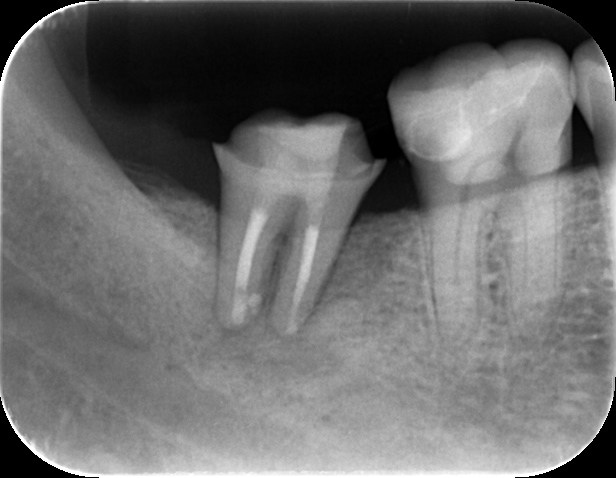

治療後3ヶ月のレントゲンで、歯の根の周りの骨が回復してきているのが確認されます。治癒の経過は仮の被せを装着して噛める状態で確認していきます。

治療後1年。歯の周りをしっかりと骨が取り囲み、良好な治癒が確認されます。